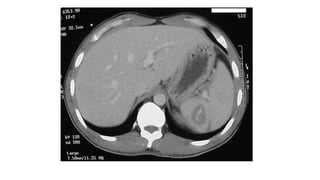

TAC

• Se debe de utilizar solo en el paciente estable.

• Evalúa el bazo y los órganos vecinos.

• Se utiliza contraste i.v., sin contraste puede no identificar un sangrado

intraparenquimatoso.

TAC • Se debede utilizar solo en el paciente estable. • Evalúa el bazo y los órganos vecinos. • Se utiliza contraste i.v., sin contraste puede no identificar un sangrado intraparenquimatoso.